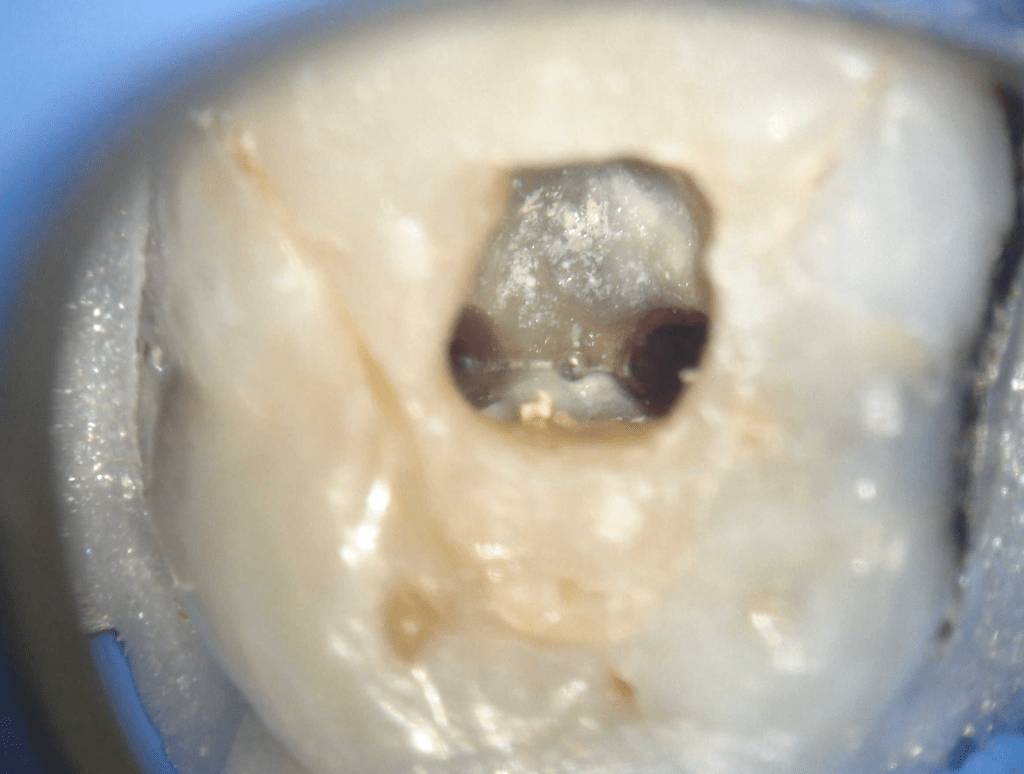

Fisura, remoción amalgama para explorar